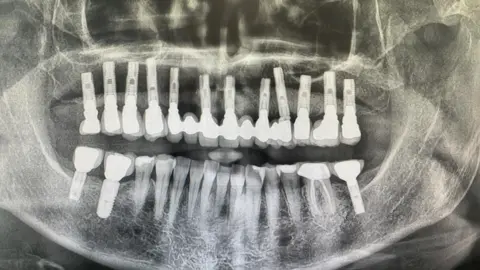

“But the main reason I quit was because I lost most of my top teeth due to gum disease," she said, adding they would fall out when she would bite on food, sometimes something even as soft as a roll.

Her dentist told her that her mouth had been starved of oxygen and smoking had been a key factor.

After some failed attempts with dentures, she invested in dental implants.

Her dental surgeon had told her she would "categorically" not carry out the operation if Ms Howes had not given up smoking completely.